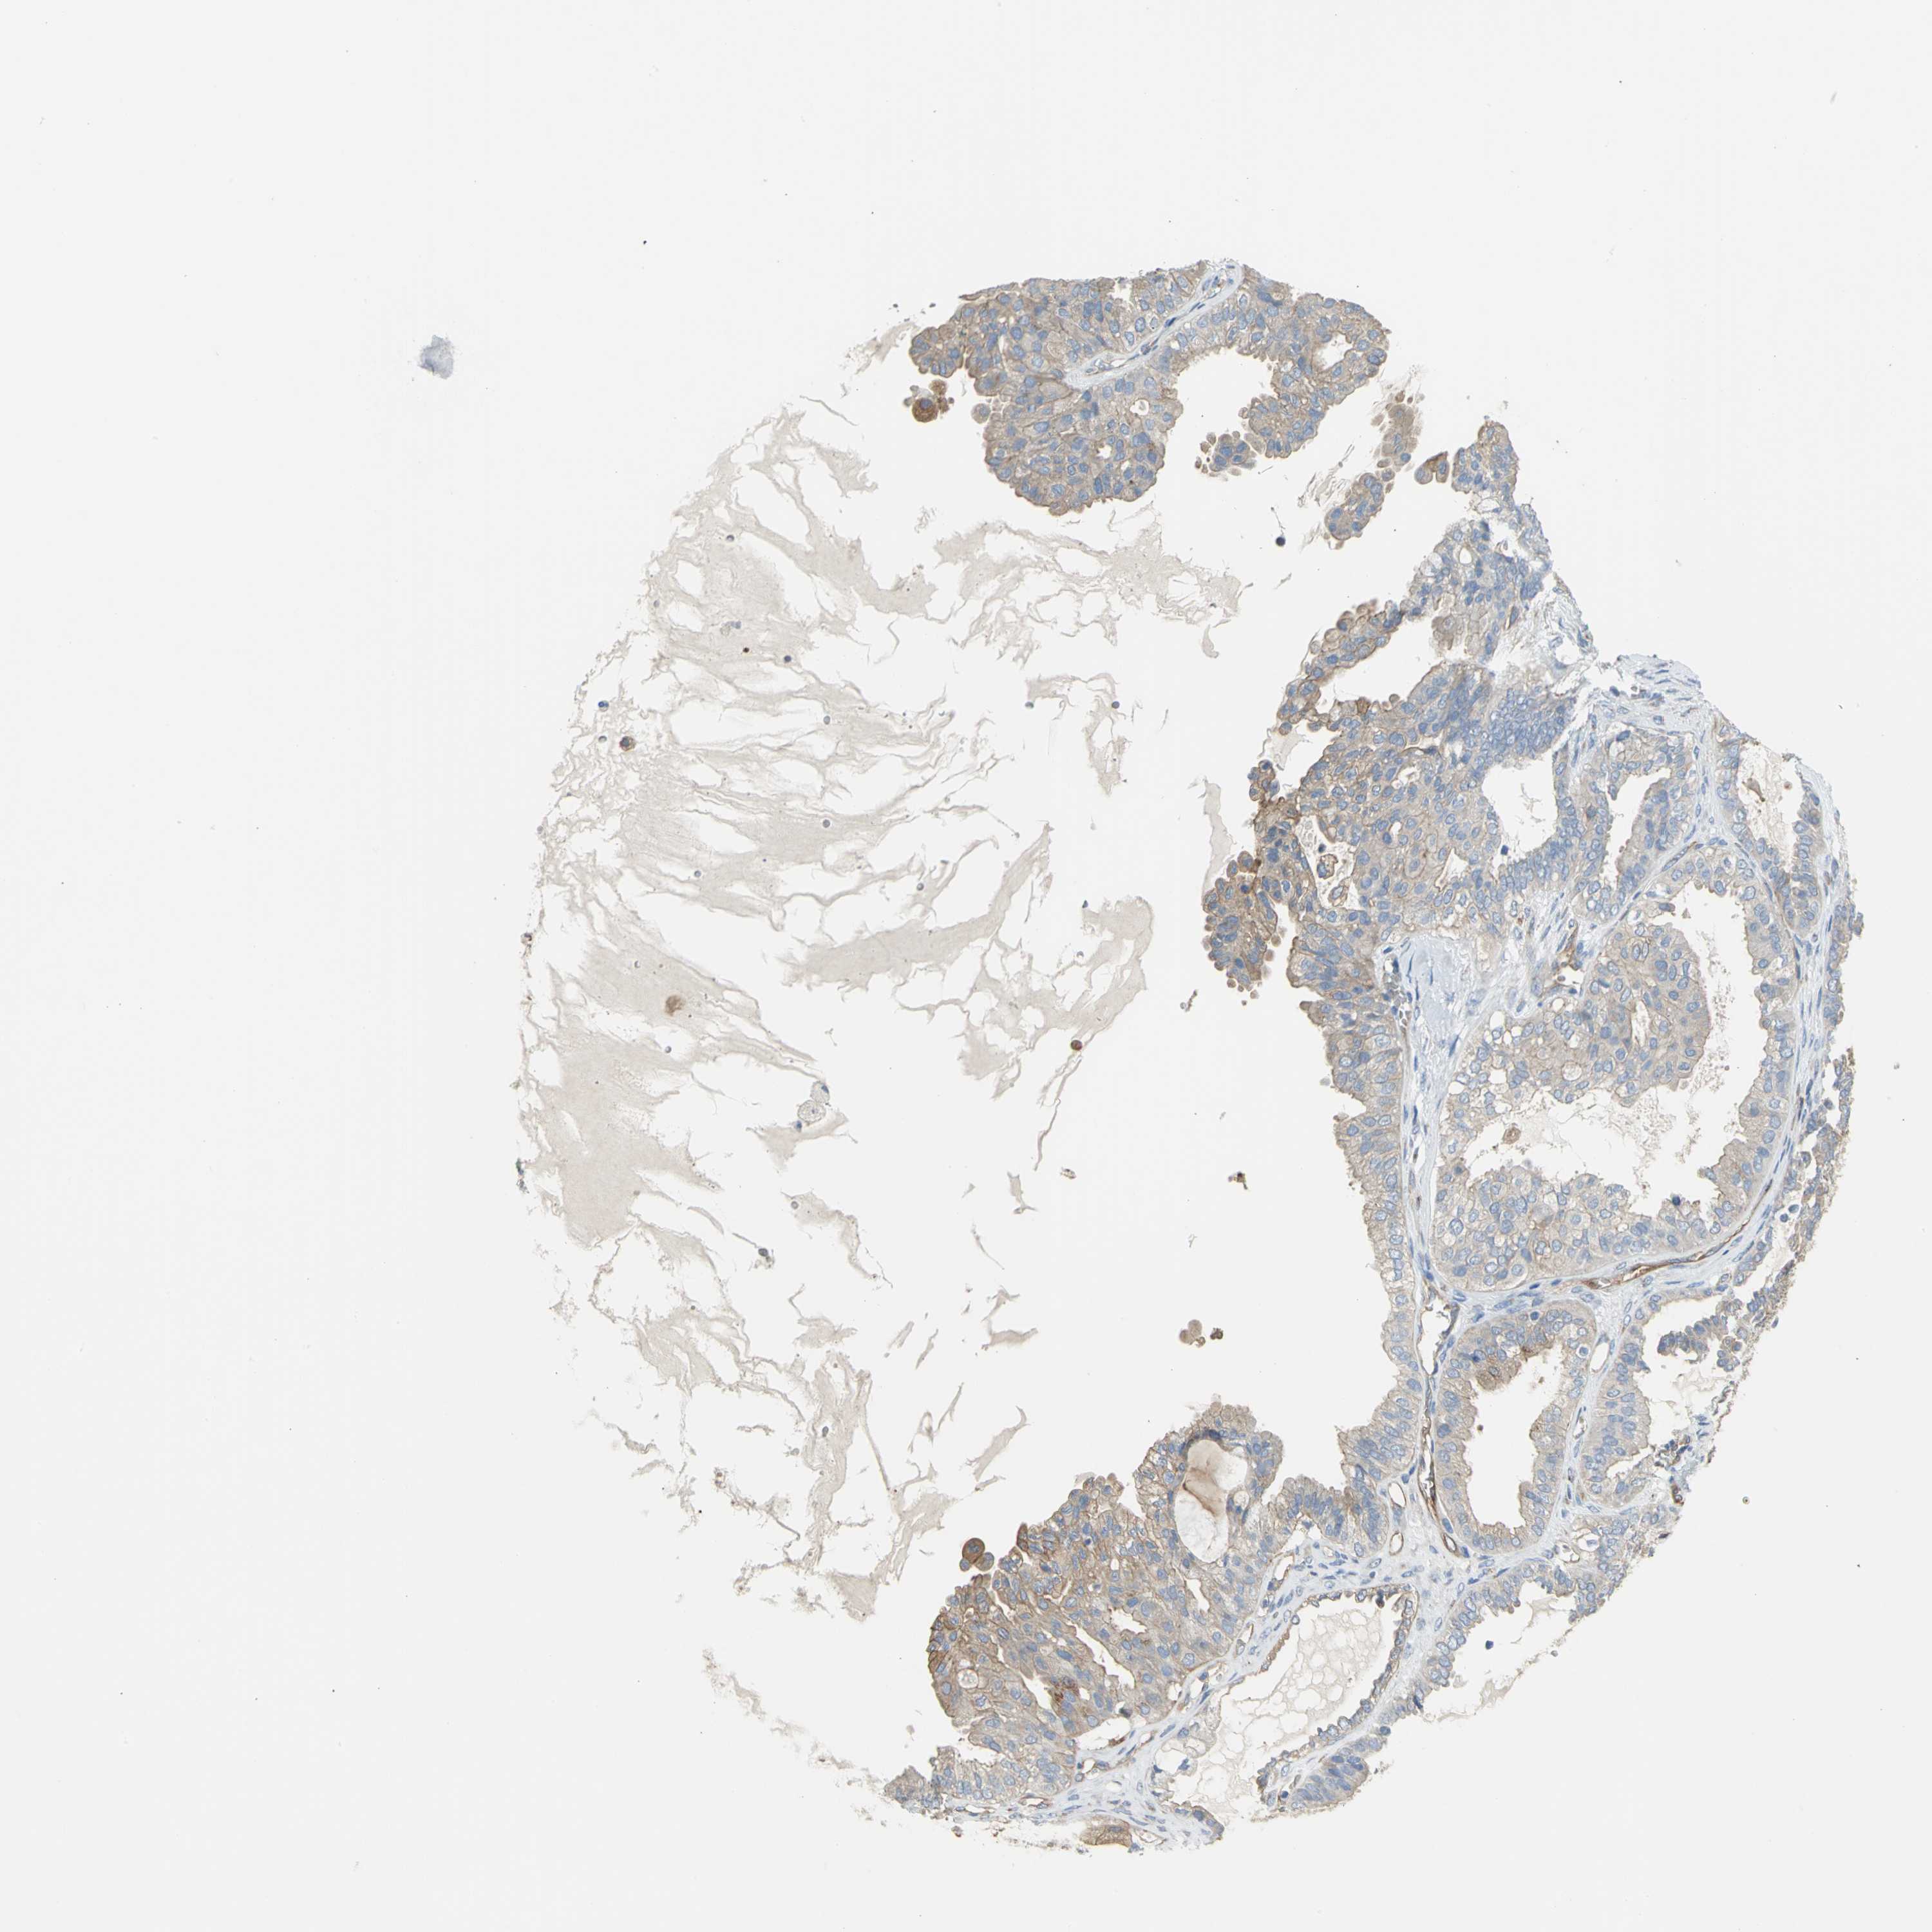

OVARIAN CANCER - Protein expressioni

A mouse-over function shows sample information and annotation data. Click on an image to view it in a full screen mode. Samples can be filtered based on level of antibody staining by selecting one or several of the following categories: high, medium, low and not detected. The assay and annotation is described here.

Note that samples used for immunohistochemistry by the Human Protein Atlas do not correspond to samples in the TCGA dataset.

Antibody stainingi

Antibody staining in the annotated cell types in the current human tissue is reported as not detected, low, medium, or high, based on conventional immunohistochemistry profiling in selected tissues. This score is based on the combination of the staining intensity and fraction of stained cells.

Each image is clickable and will lead to virtual microscopy that enables deeper exploration of all samples and also displays staining intensity scores, fraction scores and subcellular localization as well as patient and tissue information for each sample.

Antibody HPA004747

Antibody HPA004886

Antibody CAB019322

Cystadenocarcinoma, serous, NOS

Carcinoma, endometroid

Carcinoma, NOS

Cystadenocarcinoma, mucinous, NOS